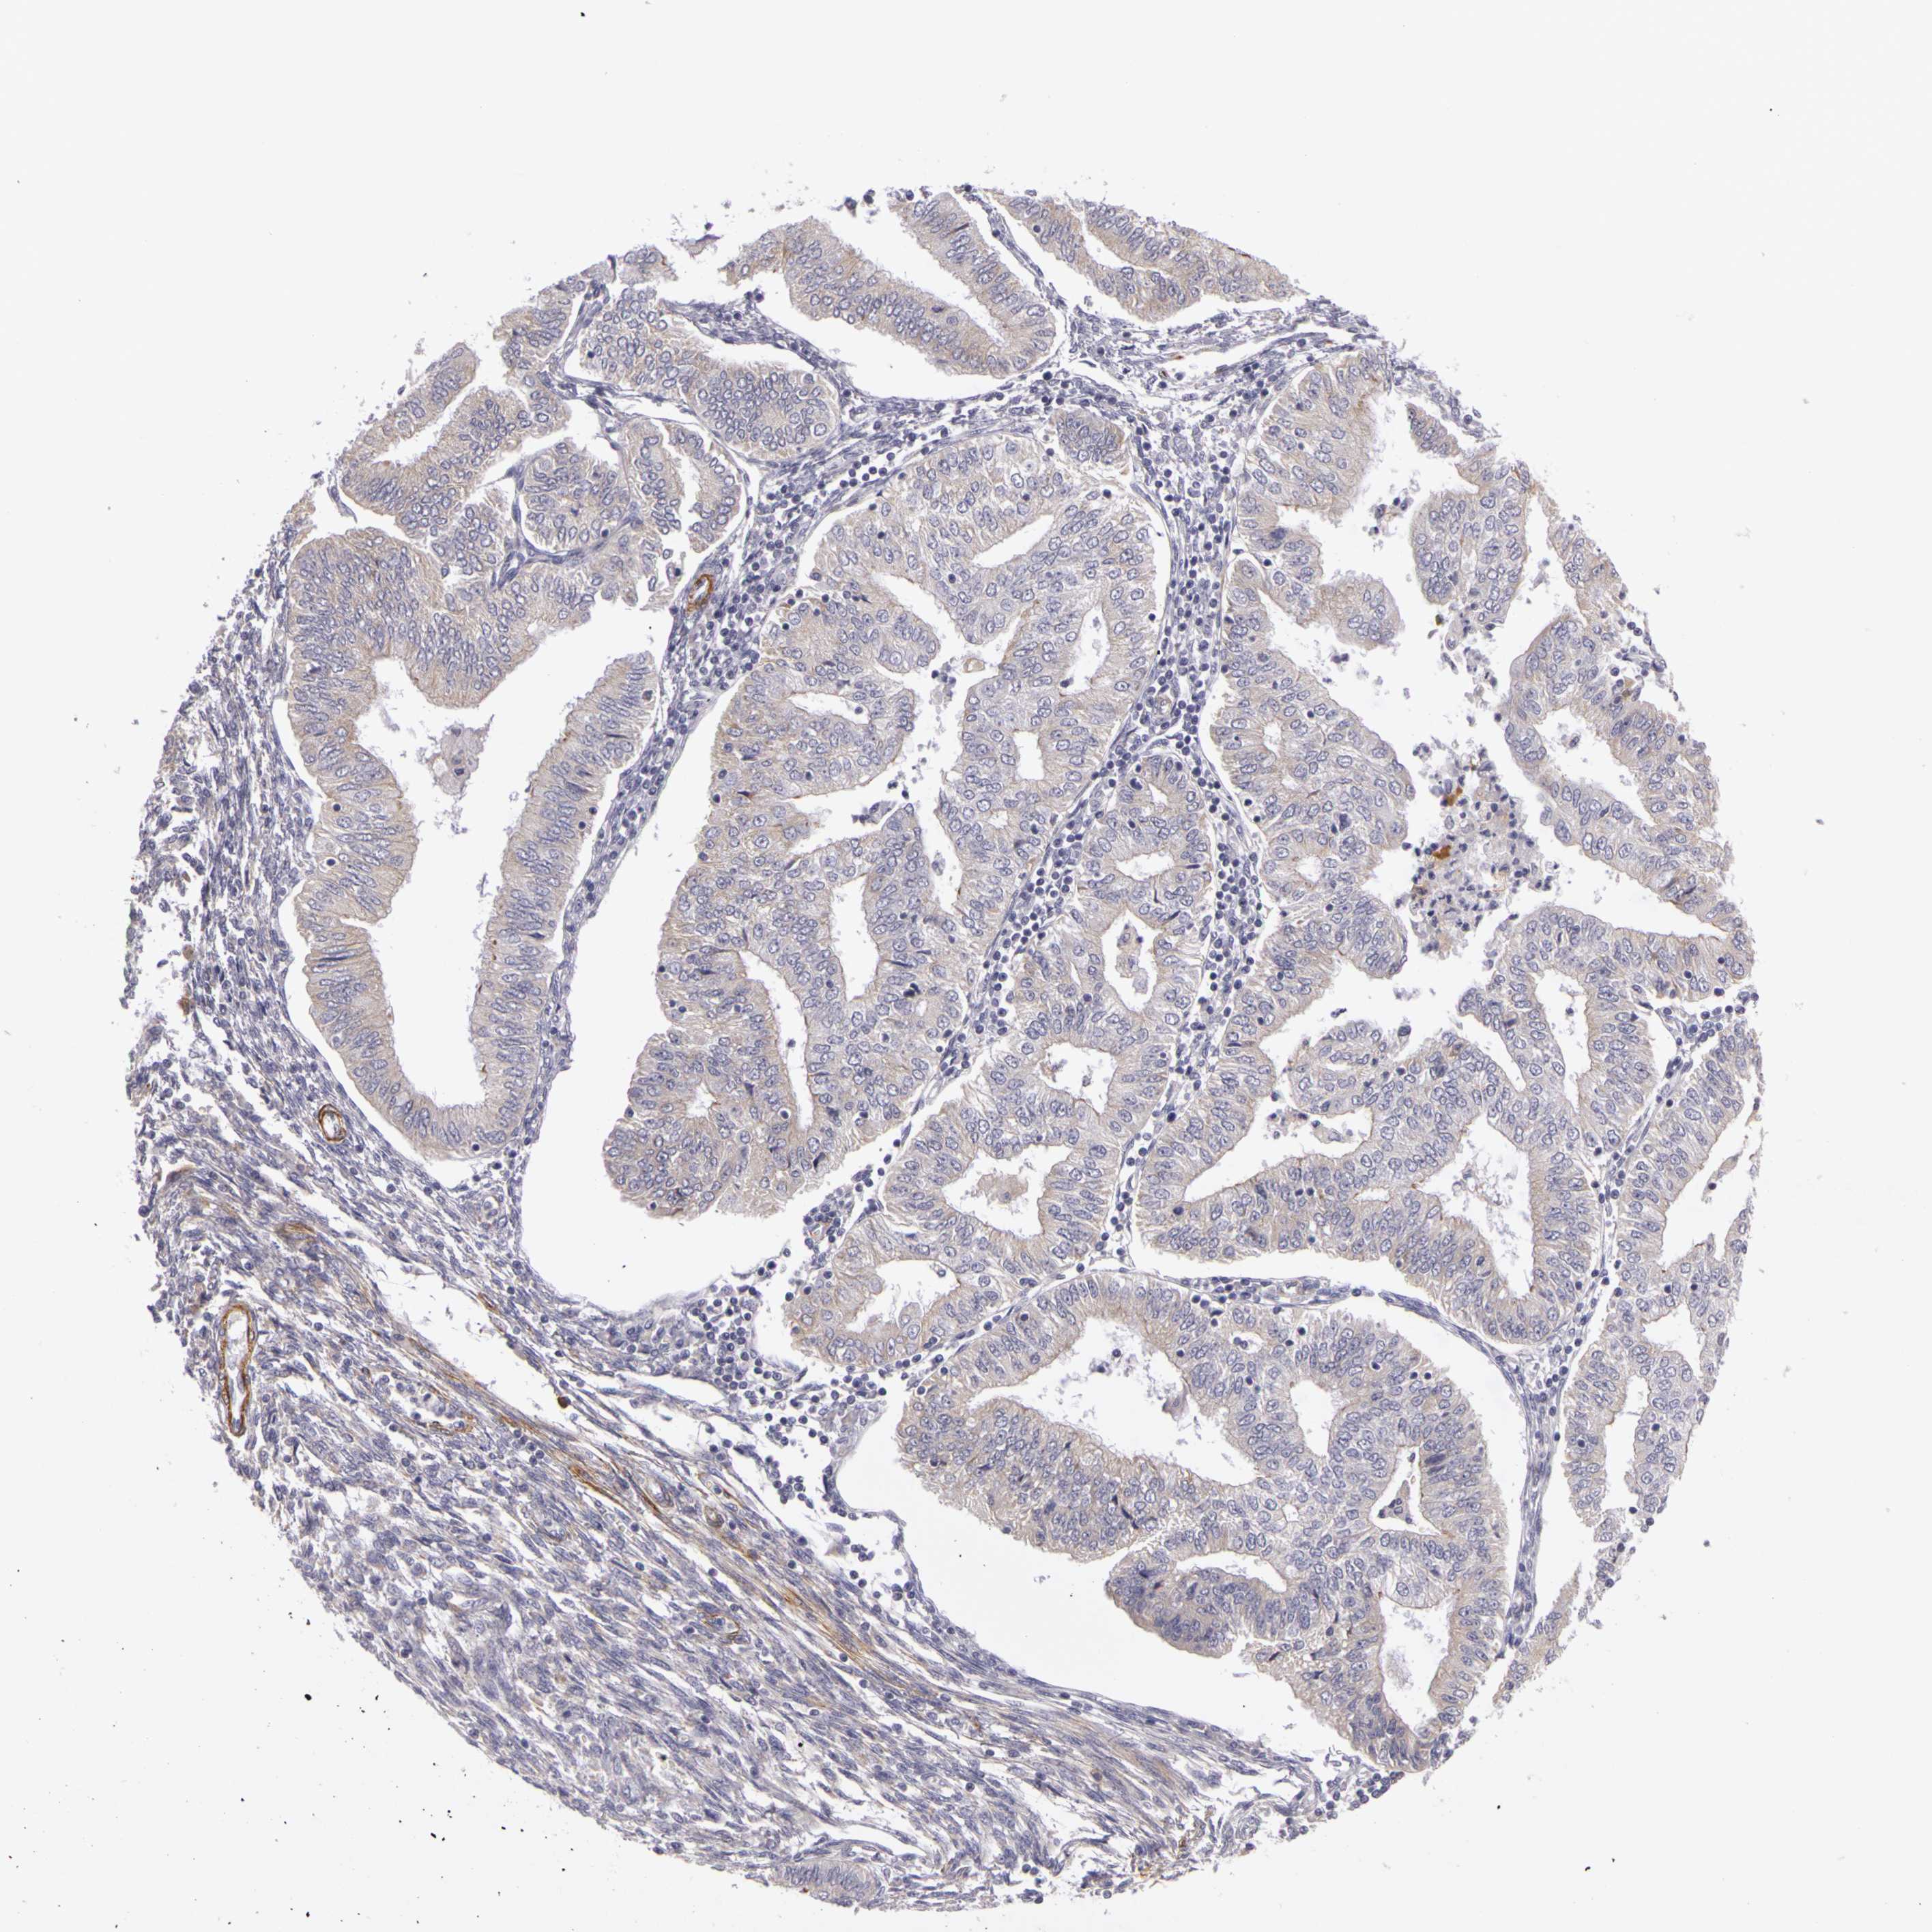

ENDOMETRIAL CANCER - Protein expressioni

A mouse-over function shows sample information and annotation data. Click on an image to view it in a full screen mode. Samples can be filtered based on level of antibody staining by selecting one or several of the following categories: high, medium, low and not detected. The assay and annotation is described here.

Note that samples used for immunohistochemistry by the Human Protein Atlas do not correspond to samples in the TCGA dataset.

Antibody stainingi

Antibody staining in the annotated cell types in the current human tissue is reported as not detected, low, medium, or high, based on conventional immunohistochemistry profiling in selected tissues. This score is based on the combination of the staining intensity and fraction of stained cells.

Each image is clickable and will lead to virtual microscopy that enables deeper exploration of all samples and also displays staining intensity scores, fraction scores and subcellular localization as well as patient and tissue information for each sample.

Antibody HPA001397

Antibody HPA012497

Staining

High

Medium

Low

Not detected

Intensity

Strong

Moderate

Weak

Negative

Quantity

>75%

75%-25%

<25%

None

Location

Nuclear

Cytoplasmic/membranous

Cytoplasmic/membranous,nuclear

Adenocarcinoma, NOS